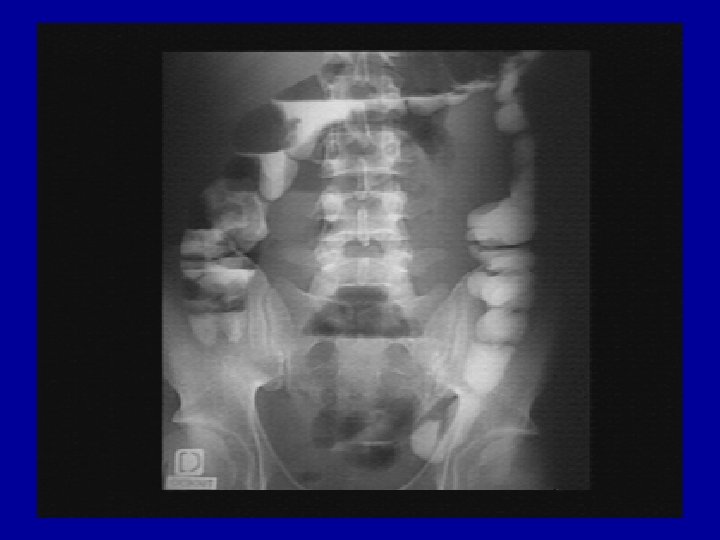

Les Explorations morphologiques de l’appareil digestif • Les techniques radiologiques – Radiologie sans préparation : ASP – Les radiologies avec contraste • • • TOGD Lavement Baryté Transit du Grêle Echographie abdominale Examen tomodensitométrique abdominal Imagerie par Résonance magnétique

Les radiologies avec contraste • avec soit ingestion, soit lavement de produits de contraste radio opaques • ont été largement détrônées par l’endoscopie digestive. • Les produits de contrastes utilisés sont – soit de la baryté – soit des hydrosolubles, utilisables même en cas de perforation • Ces produits en remplissant le tube digestif le rende visible aux rayons X et permettent ainsi d’étudier la morphologie des différents segments digestifs et de recher des pathologies par la découverte – soit d’image d’addition (ulcère, fistule…) – soit d’image de soustraction (obstacle, polype…) • Ces examens sont dynamiques et les clichés doivent être multiples en variant les incidences (face, profil, ¾) • On pourra s’aider de techniques de radio cinéma et de compressions extrinsèques • Ces examens nécessitent le jeûne et pour la plus part une préparation (vidange colique)

TOGD – LB - Transit